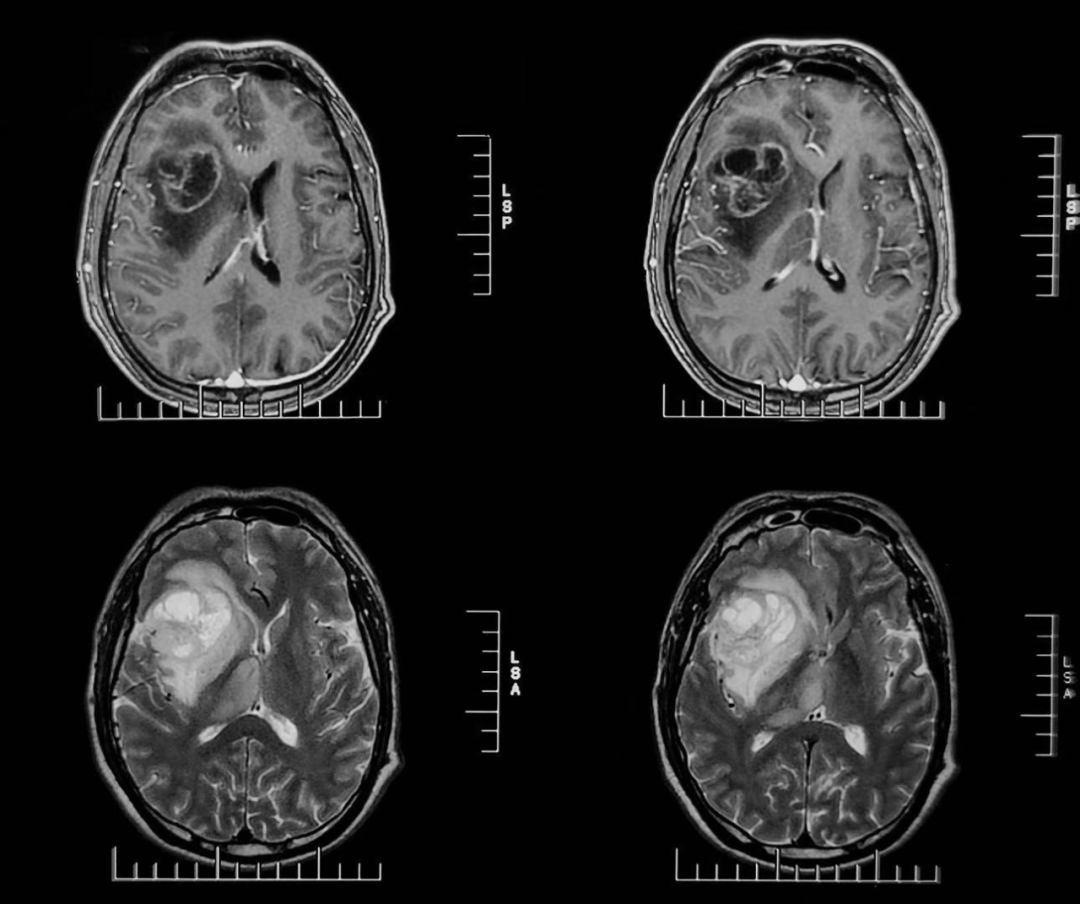

56歲的周先生(化姓)因頭痛一周入院。經(jīng)過詳細(xì)的MRS檢查,提示右側(cè)額顳島葉-放射冠-基底節(jié)區(qū)及右側(cè)丘腦異常信號(hào),MRS顯示右側(cè)病變感興趣區(qū)局部異常譜線,符合腫瘤譜線特征。綜合考慮高級(jí)別膠質(zhì)瘤可能性大,膠質(zhì)母細(xì)胞瘤。

▲患者術(shù)前MRS影像